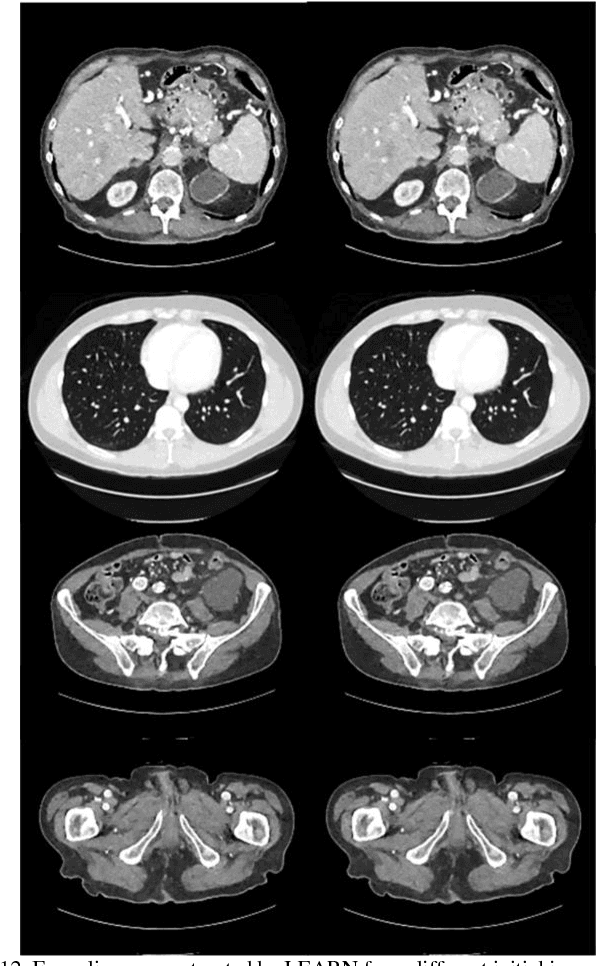

Abstract:Compressive sensing (CS) has proved effective for tomographic reconstruction from sparsely collected data or under-sampled measurements, which are practically important for few-view CT, tomosynthesis, interior tomography, and so on. To perform sparse-data CT, the iterative reconstruction commonly use regularizers in the CS framework. Currently, how to choose the parameters adaptively for regularization is a major open problem. In this paper, inspired by the idea of machine learning especially deep learning, we unfold a state-of-the-art "fields of experts" based iterative reconstruction scheme up to a number of iterations for data-driven training, construct a Learned Experts' Assessment-based Reconstruction Network ("LEARN") for sparse-data CT, and demonstrate the feasibility and merits of our LEARN network. The experimental results with our proposed LEARN network produces a competitive performance with the well-known Mayo Clinic Low-Dose Challenge Dataset relative to several state-of-the-art methods, in terms of artifact reduction, feature preservation, and computational speed. This is consistent to our insight that because all the regularization terms and parameters used in the iterative reconstruction are now learned from the training data, our LEARN network utilizes application-oriented knowledge more effectively and recovers underlying images more favorably than competing algorithms. Also, the number of layers in the LEARN network is only 12, reducing the computational complexity of typical iterative algorithms by orders of magnitude.